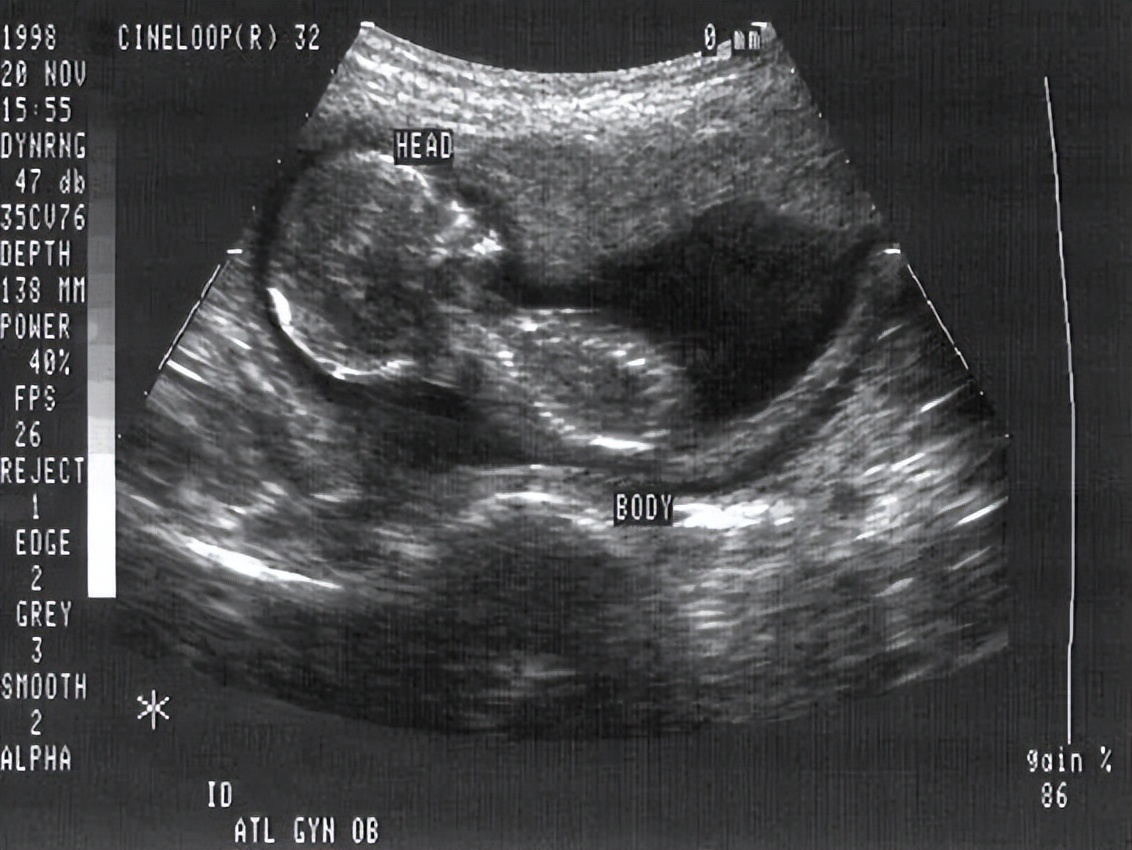

▲ 孕妇怀孕期间的B超图像

如果我们认真来拆解,其实会发现“机器人妈妈”主要有两个组成部分:一个机器人本体,一个人造子宫。

而在生育这件事情上,人造子宫既是重点,又是难点。